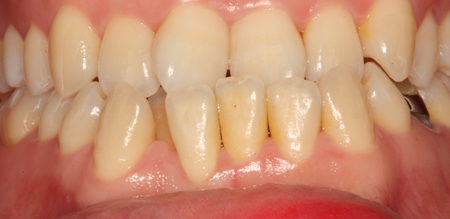

치주치료

청담네오플란트는 치주치료를 통하여 치아를 살릴 수 있는 기회를 놓치지 않습니다.

치주염(잇몸병)은 치아에 붙어있는 치석 및 세균 등에 의한 염증반응으로 잇몸뼈가 상실되는 질환을 말합니다.

초기에는 잇몸이 붓거나 잇몸에서 피가 나는 증상이 나타나며 계속 방치하면 치아를 발치해야 할 수도 있습니다.

치주치료는 이러한 치석 및 세균 등을 제거하여 잇몸뼈를 안정된 상태로 유지하는 시술을 말하며, 청담네오플란트에서는 치의학박사 / 전문의가 직접 시술하고 있습니다.

치주염 단계별 증상

건강한 상태

치아 주위의 잇몸이 핑크색을 띄며, 잇몸에서 피가 나지 않음.

스케일링을 6개월 ~ 1년 주기로 받고 올바른 칫솔질로 건강한 치주 조직을 유지

치은염 (초기~중기)

치아 주위의 잇몸이 붉게 부어 있으며, 칫솔질 등을 할 때 피가 남.

스케일링 주기의 조절이 필요할 수 있으며, 올바른 칫솔질을 시행하여야 함.

치주염 (중기~말기)

주기적으로 잇몸이 붓고 피가 나며, 욱씬하거나 우리한 통증이 나타남.

치주치료 및 정도에 따라 치주수술(잇몸수술)이 필요함. 향후 관리 정도에 따라 3~6개월 간격으로 내원하여 유지치료를 시행하여야 함.

치주염 (말기)

잇몸이 항상 부어 있으며, 이가

흔들리는 정도가 점점 심해짐.

치주치료가 필요하며, 정도에 따라 치아를 발치하여야 할 수 있음.

치주치료 전후사진

B

A